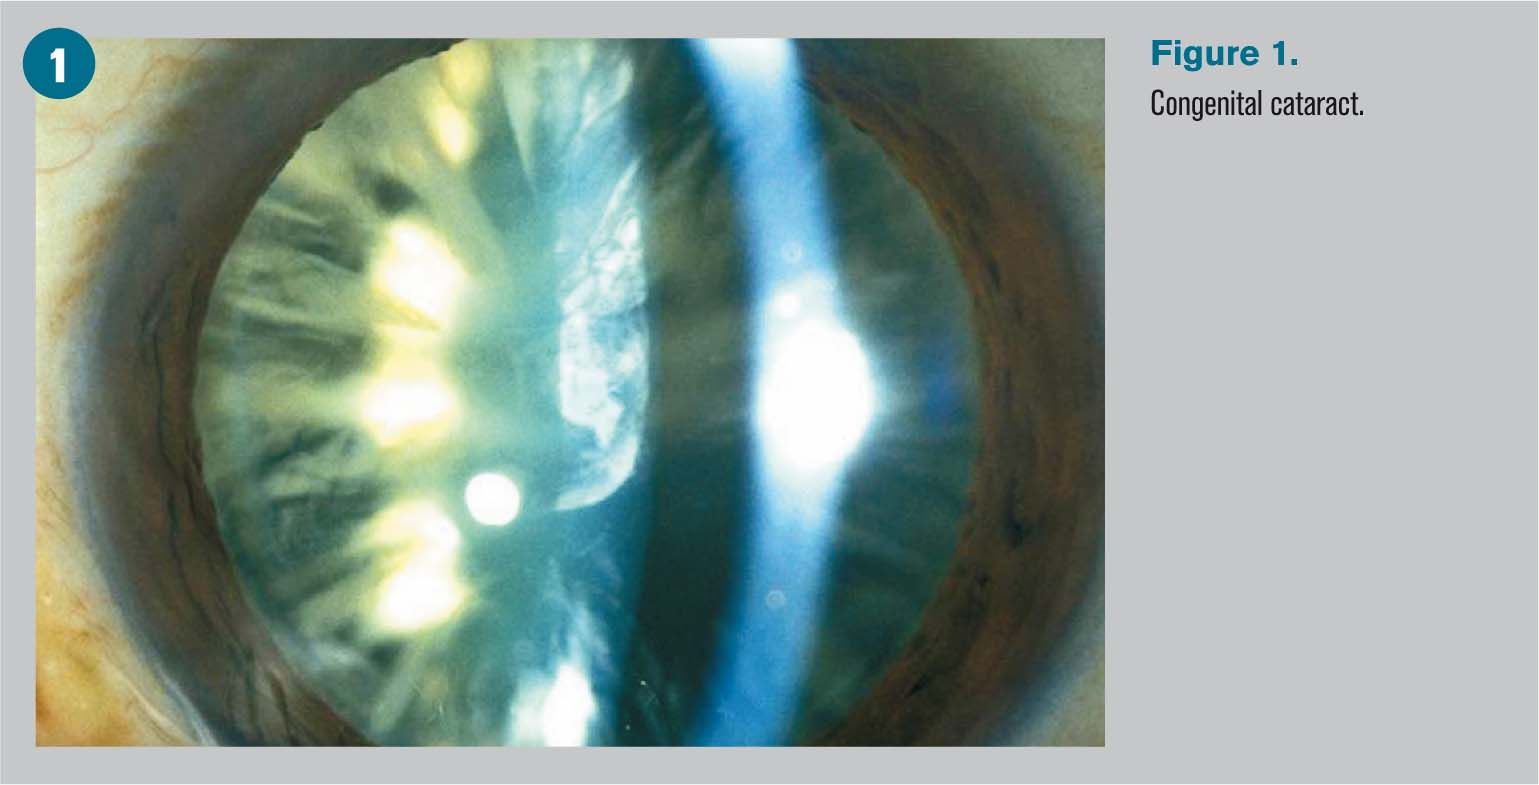

Диагностика катаракты: биомикроскопия и её значение